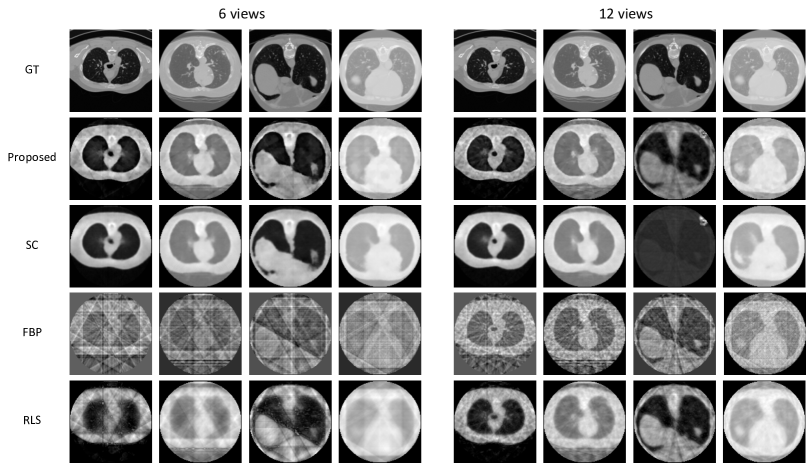

Figure 2 shows qualitative results from two different views, 6 and 12, respectively. We observe that the proposed method yields sharper edges and more high frequency regions with less artifact and noise, compared to the baseline algorithms. Figure 3 shows quantitative evaluation on 6 different few-view experiments (3, 6, 9, 12, 15, 18 views). PSNR and SSIM show that the proposed approach outperforms the baselines although both metrics are not sufficient to measure perceptual quality. Another observation is that RLS improves the image quality as the number of views increases while our method outperforms by a large margin especially when the number of views is extremely small.